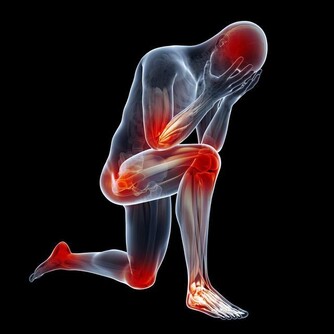

TOP1爬樓梯

進入老年後,人體肌肉會減少3%-5%,關節開始退化,上下樓梯或者爬山時,

膝關節承受人體重量是平時的3-5倍,這會加重關節老化。